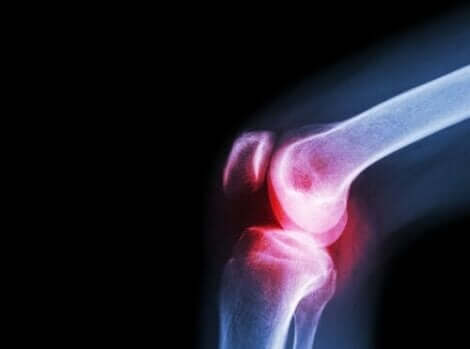

Άλλο ένα συχνό σύμπτωμα του συστηματικού ερυθηματώδη λύκου είναι ο πόνος στις αρθρώσεις. Αυτός προέρχεται από την αρθρίτιδα που ενεργοποιείται από την αυτοάνοση αντίδραση του σώματος. Η πρόοδος της αρθρίτιδας έρχεται με σοβαρά επεισόδια και περιόδους με και χωρίς πόνο.